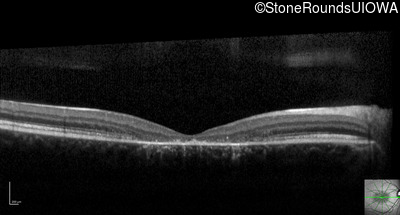

Optical Coherence Tomography - Left - 10/125 -1

Exemplar / OCT Stack

OCT Stack